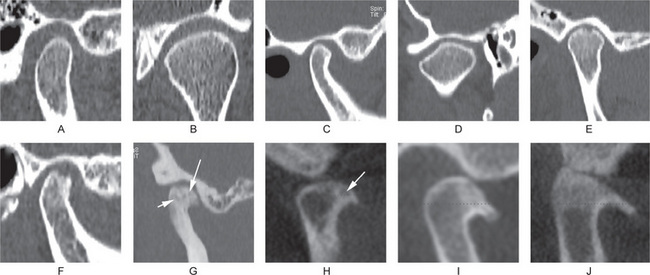

Figure 17-44 Computed tomographic findings of normal and osteoarthritic temporomandibular joints.

(A) Sagittal view of a normal temporomandibular joint, which has smooth, rounded and well-defined cortical margin of the condyle and the fossa. (B) Axially corrected coronal view of a normal temporomandibular joint which has smooth, rounded and well-defined cortical margins. (C) Sagittal view of a temporomandibular joint that shows signs of remodeling. Anterior slope of the condylar head is flat. (D) An axially corrected coronal view showing remodeling of the condylar head. The lateral slope of the condylar head is flat. (E–J) Images of joints with degenerative joint disease. (E, F) Sagittal views showing erosion of the condylar heads. The continuity of the cortical margin is lost. (G) A condyle with generalized sclerosis, osteophyte at the anterior margin, and several subcortical pseudocysts (arrows). (H–J) From cone beam computed tomography. (H) An osteophyte at the anterior margin of the condylar head and a subcortical pseudocyst (arrow). (I) A prominent osteophyte, which often appears as a bird’s beak. (J) A prominent anterior osteophyte, sclerosis of the superior part of the condylar head, and flattening of the articular eminence.